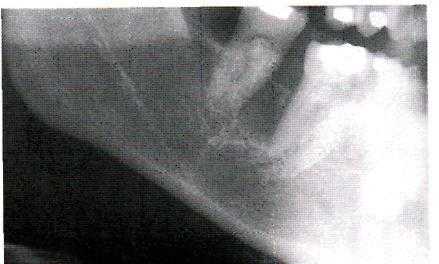

Рентгенологическая картина опухолевых поражений челюстных костей немногочисленна, это деструкция, деформация кости и периостальная реакция. Деструкция наблюдается в виде одиночного (фиброма, миксома, энхондрома, остеобластокластома, остеогенная саркома и др.) и множественных очагов (эозинофильная гранулёма, полиоссальная фиброзная дисплазия). Форма очагов деструкции может быть округлая, продолговатая, неправильная, очаги деструкции могут локализоваться в любом участке кости челюсти, располагаясь центрально или периферически.

Характер границ довольно типичен: так, остеома является прямым продолжением кортикального слоя и сливаясь с ним, располагается на поверхности кости. Очаг фиброзной дисплазии, располагаясь внутрикостно, имеет обычно четкую границу в виде склеротической каемки.

Для эозинофильной гранулёмы характерны многофестончатые «штампованные» границы.

Остеобластокластома в случае кистозной формы окружена со всех сторон зоной склеротической ткани, а при литической форме в направлении продолжающего роста границы теряют четкость.

Деформация кости проявляется вздутием, если новообразование находится внутри кости, утолщением за счет периостальных наслоений или в виде дополнительных образований, исходящей из кости (остеома, экхондрома). Однако патогномоничной для доброкачественной первичной костной опухоли челюстей не существует.